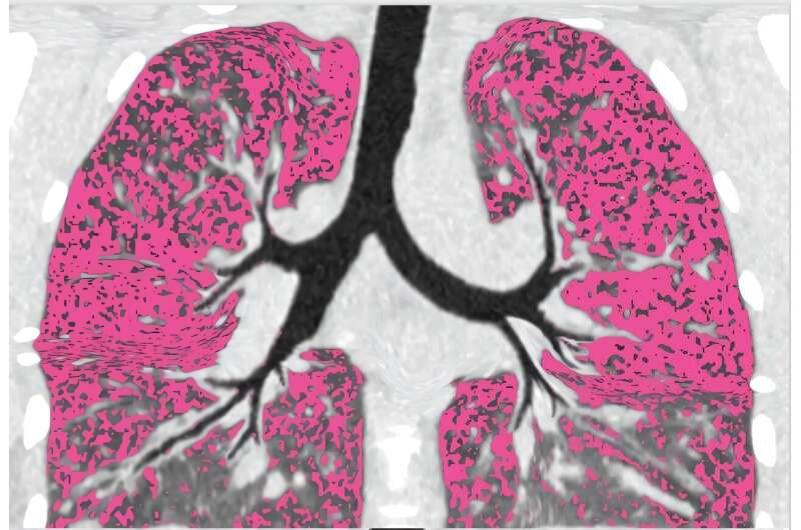

До сих пор врачи полагали, что причина хронических инфекций при муковисцидозе — повреждённые участки лёгких, где бактерии словно «укрываются». Но новое исследование опровергло эту картину.

Работа учёных из Университета Вашингтона и Университета Айовы, опубликованная в журнале Cell Host & Microbe, показала: инфекция сохраняется даже в тех частях лёгких, которые выглядят почти здоровыми.

• если инфекция сохранялась, то она присутствовала повсюду — даже в наименее повреждённых сегментах.

📌 Главная идея: не только повреждённая ткань удерживает бактерии. При муковисцидозе инфекция может сохраняться даже там, где лёгкие выглядят здоровыми.